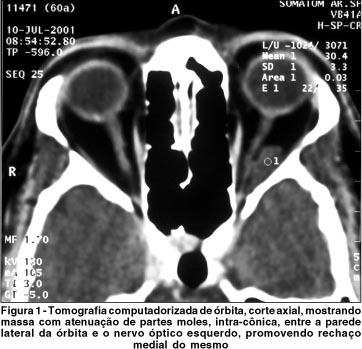

A tomografia computadorizada orbitária e a ressonância nuclear magnética mostraram massa intra-cônica à esquerda, fusiforme, de contornos bem definidos, medindo cerca de 1,8 x 0,8 cm, localizada entre o nervo óptico e o músculo reto lateral esquerdo, borrando os contornos desse músculo (Figura 1 e 2).